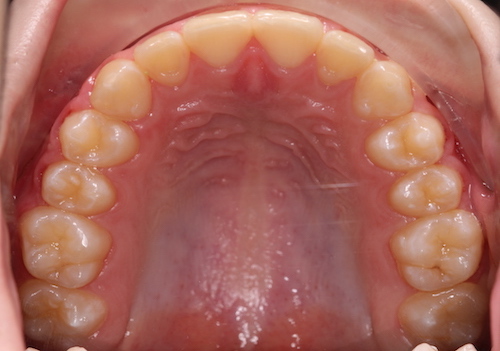

После